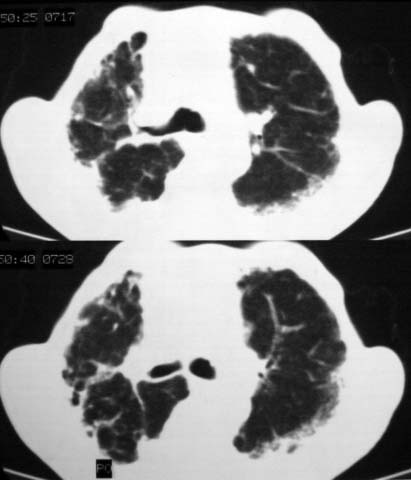

男,85岁,发热2月, 血常规:hgb99g/l.rbc2.55×1012/l.wbc3.8×109/l.n78.2%  l20.7% m1.1%.  hct26.3% .血沉20mm/hg.痰检结核杆菌阴性。ddp阳性。痰少粘稠色白。无咳血。

1.右上肺陈旧性肺结核灶;

双肺结核

右上肺陈旧性肺结核灶,双肺感染灶〔大部份纤维化〕,肺气肿.

两肺陈旧性tb

双肺继发型结核

双肺继发型肺结核,肺纤维化,肺气肿,胸膜肥厚黏连。